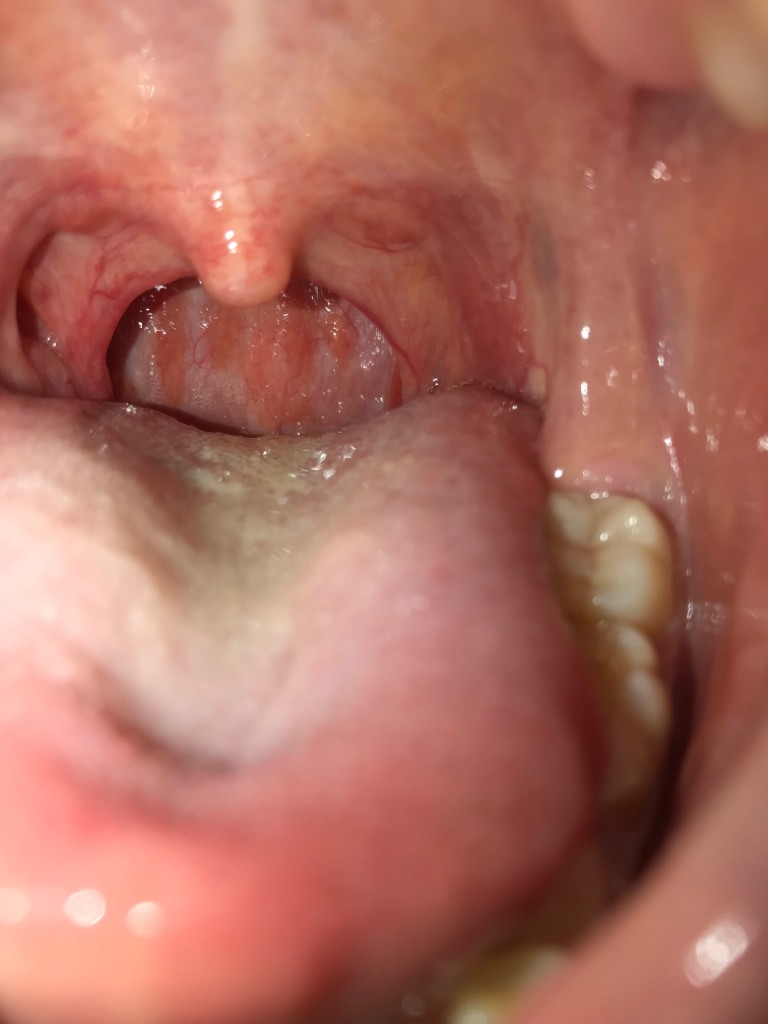

염증주사 이런거 맞으면 나을까요??ㅠㅠ 목은 많이 부은건가요? 약은 아래와 같이 처방받았습니다.. 어떻게 하면 호전될까요

사진으로 보아서는 염증이 심하지 않습니다

목의 붓기는 심하지 않은 편이며, 일부 염증이 있으신 것 같습니다.